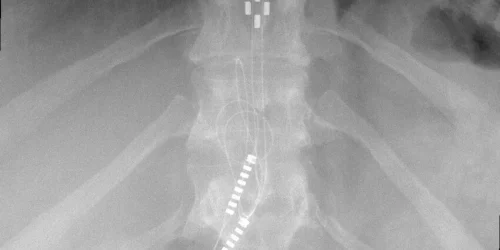

MRI is the most useful imaging study for back pain diagnosis, and it is where the diagnostic workup should start. It provides detailed visualization of soft tissue structures, including discs, ligaments, nerve roots, and spinal cord, that plain X-rays and CT scans cannot match. For identifying herniated discs, disc degeneration, spinal stenosis, nerve compression, and some facet joint changes, MRI is irreplaceable.

- Radiologists miss disc bulges from annular tears more than 50% of the time. The specific finding most associated with discogenic pain is also the one most frequently overlooked on standard MRI reads.

- Standard MRI rarely identifies inflammation in the posterior annular fibers. The exact location where disc pain originates is poorly visualized on routine sequences.

- Annular tears are not typically visible on standard MRI. The High Intensity Zone (HIZ), a white area occasionally seen in the posterior annulus, can suggest inflammation in that region, but its absence does not rule out a painful annular tear, and its presence does not confirm one.